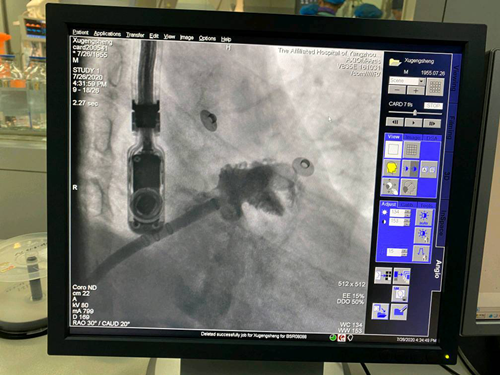

近日,我院心血管内科在超声科、麻醉科等科室的协助下,成功完成一例“房颤射频消融+左心耳封堵”一站式手术。

患者许某为男性,今年65岁。1年前被诊断为阵发性房颤,按医嘱口服抗凝药物达比加群酯。今年5、6月多次出现急性脑梗死。后入住我院心血管内科,经专家团队讨论,患者诊断为房颤所致的心源性脑栓塞。结合患者病史情况,专家们为其实施“房颤射频消融+左心耳封堵术”介入治疗。术后患者复查心电图为窦性心律,超声检查左心耳完全封堵,患者恢复良好。

据了解,“左心耳封堵术”是目前全球预防房颤患者卒中的治疗新趋势,它是通过导管将一个镍钛合金的左心耳封堵器安置在左心耳内,达到封闭左心耳的目的,从而预防左心耳内血栓脱落引起血栓栓塞事件的发生。同时,患者术后无需长期口服抗凝药物,不仅避免抗凝药出血并发症的发生,而且为患者节省医疗费用。